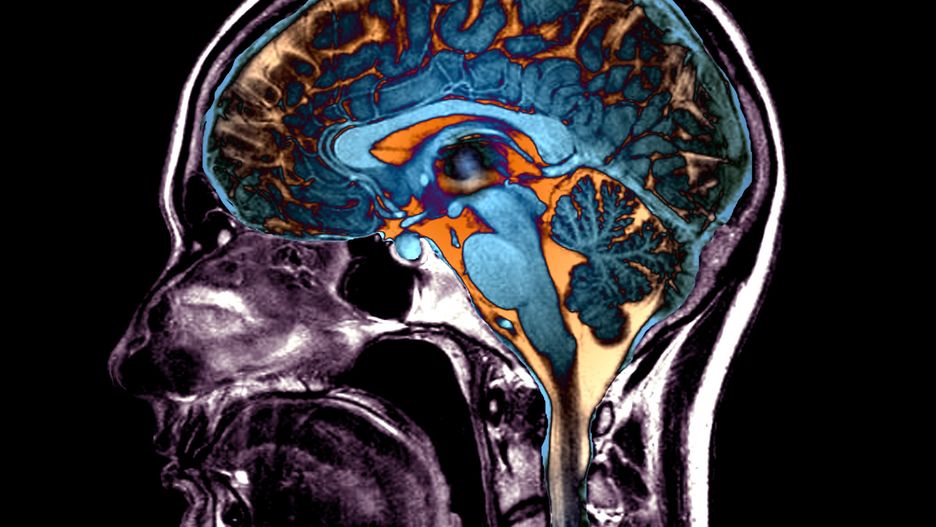

Obraz

Źródło zdjęć: © East News | ZEPHYR/Science Photo Library